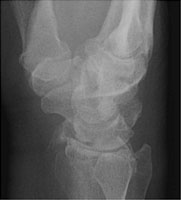

- Click on the image for a larger versionBLateral radiograph of the wrist. This shows the radial styloid fracture.